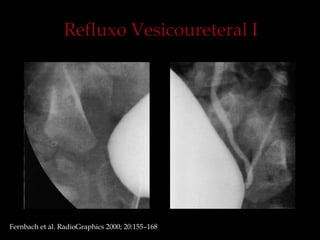

Fernbach et al. RadioGraphics 2000; 20:155–168.

Refluxo 1º: O retorno de urina da bexiga para o uréter, conseqüência de uma

anomalia congênita da junção ureterovesical.

Hipoplasia de musculatura trigonal associada à diminuição do comprimento

do ureter submucoso

Fernbach et al. RadioGraphics 2000; 20:155–168